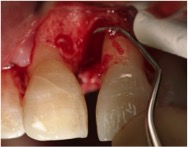

Fotos dos casos clínicos